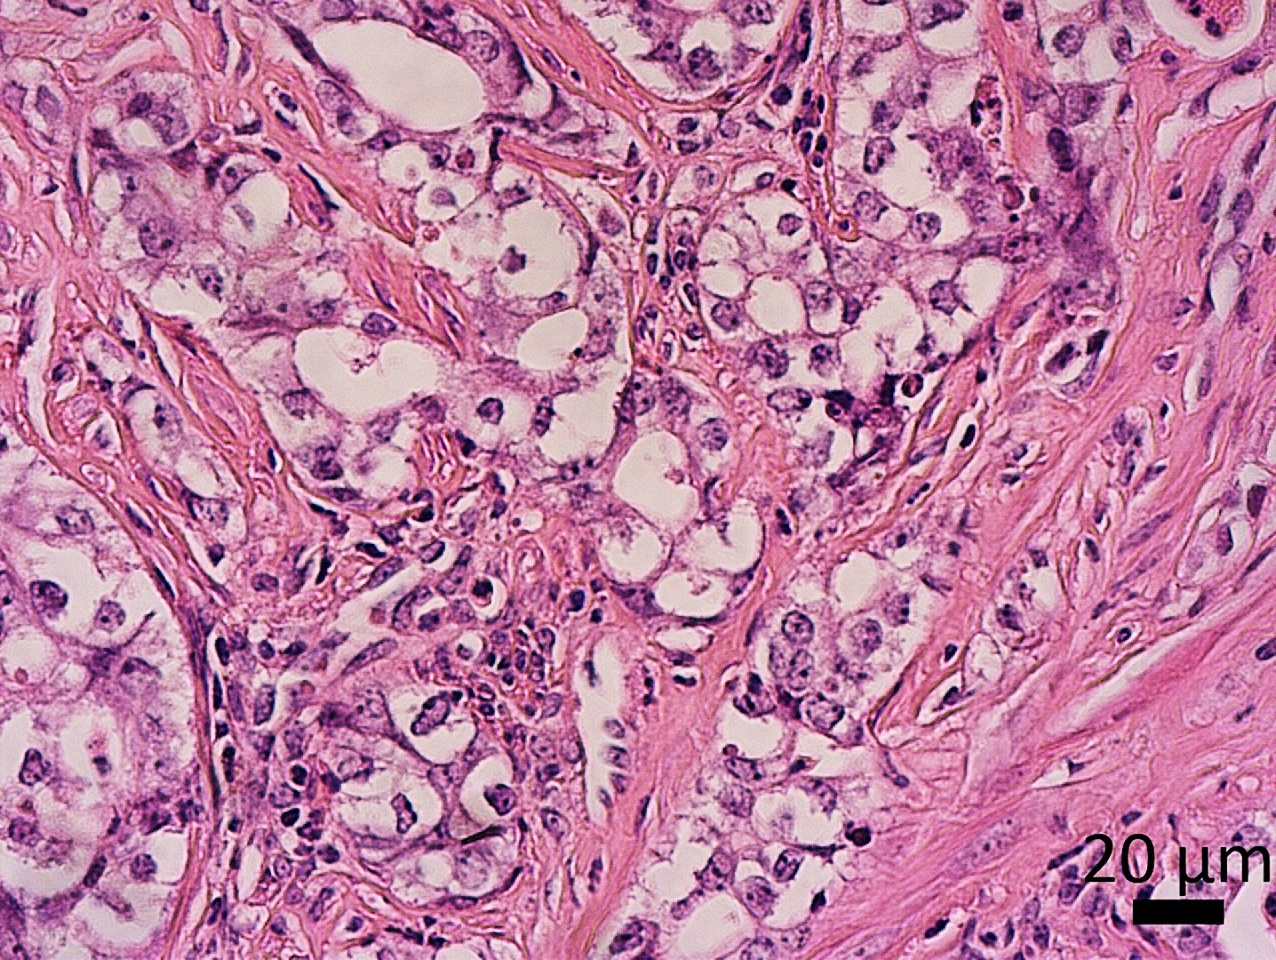

• Poorly differentiated adenocarcinoma

• Malignant cells with clear-cell features

This mouse model represents a first-of-its-kind model of poorly differentiated endometrial adenocarcinoma that develops from an atrophic endometrium caused by loss of Dicer1. This model recapitulates important steroid hormone and molecular features of human disease. We hope that these novel models will allow future studies into the rarer forms of endometrial cancer but also the development of novel therapies.